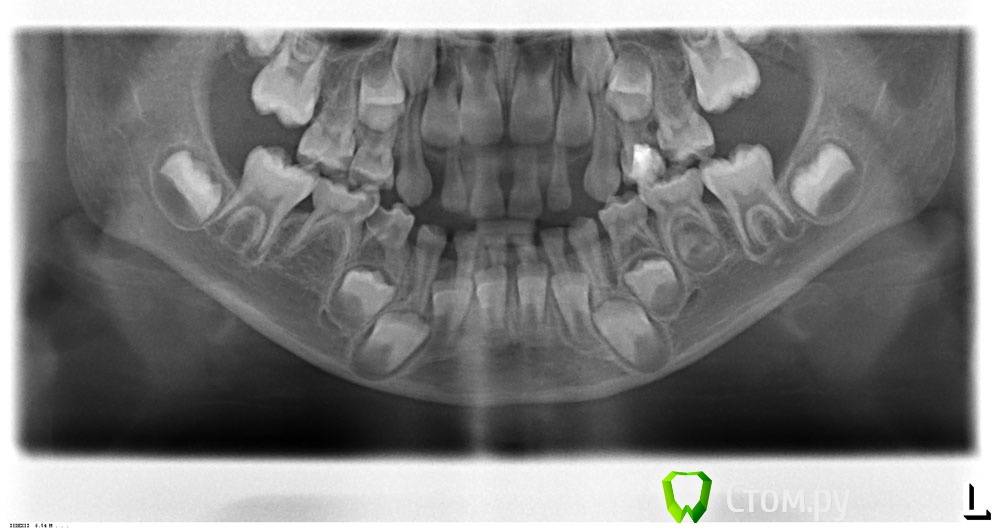

Wella Опубликовано 29 июля, 2014 Поделиться Опубликовано 29 июля, 2014 Добрый день! Прошу подсказать, можно ли сохранить 4й правый нижний зуб? (ребенку 6 лет)Зуб беспокоит, доктор рекомендует удалять.Сколько зубов здесь нужно пролечить? Мы насчитали 5 пульпитов, это так? И что можно сделать с тем, что не сформированы зачатки постоянных 5-рок снизу и сверху?Спасибо заранее. Ссылка на комментарий

Korel Опубликовано 29 июля, 2014 Поделиться Опубликовано 29 июля, 2014 можно ли сохранить 4й правый нижний зуб? (ребенку 6 лет) Лучше удалить. Мы насчитали 5 пульпитов, это так? Считать пульпиты лучше очно)) И что можно сделать с тем, что не сформированы зачатки постоянных 5-рок снизу и сверху? Если не сформированы, то пока ничего. Ссылка на комментарий